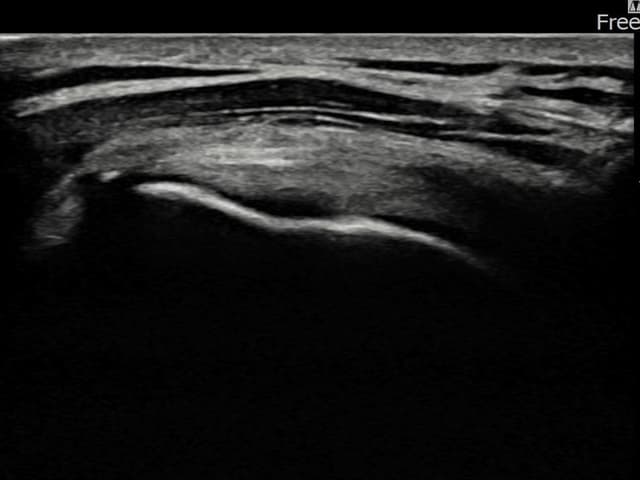

[촬영시기:22.08.29~22.12.23]

[어깨인대 축소봉합술] 우측 어깨 전방 통증과 팔 내회전 제한으로 내원하셨습니다.